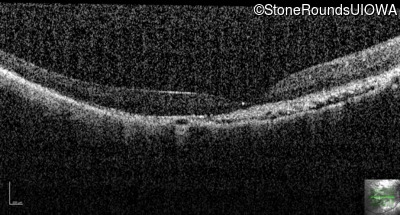

This 12 year old girl has had poor night vision and subnormal acuity since she was about 3 years old.

| Age at visit: 12 years (Visit 2) |